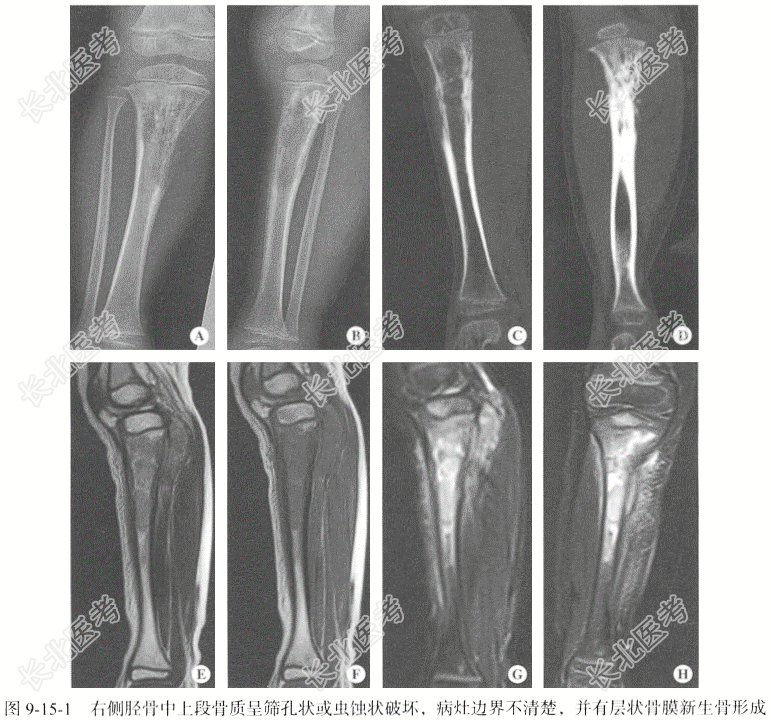

- [材料题] 【临床病史】女性,14岁。右侧小腿近端疼痛1年余,肿胀3个月。

【专科查体】右侧膝关节下方软组织肿胀,局部皮温较对侧稍高,局部无红肿,无破溃,局部压痛。

【影像检查】右侧胫腓骨DR正侧位;右侧胫腓骨CT扫描,层厚为3mm,层间隔3mm,行CT矢状位、冠状位重建;右侧胫腓骨MRI扫描,包括T₁WI、T₂WI及T₂WI脂肪抑制序列,扫描层厚为5mm,层间隔5mm;辅以冠状位T₂WI,矢状位T₂WI脂肪抑制序列。

【影像图片】见图9-15-1。

【病理诊断】尤因肉瘤。